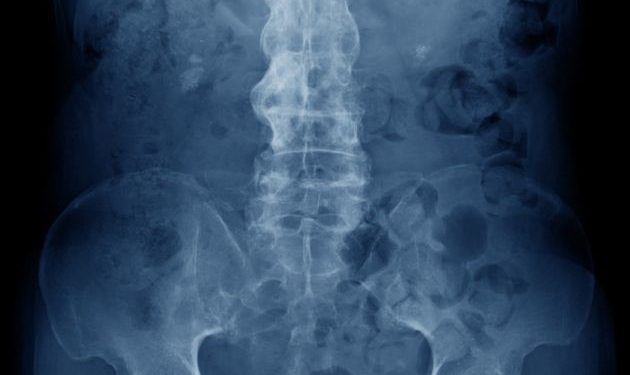

Diagnosis is a complex process and can involve a combination of tests, including a physical examination, blood work, and X-rays or other imaging studies. Your doctor can also ask you about your medical history, family history, and any other conditions that you might have. You might be asked about whether you have a condition known as HLA-B27, which is linked with ankylosis spondylitis.